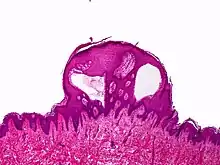

Lymphangioma circumscriptum; only stratum papillare is affected.

A biopsy of the affected skin and histological examination under the microscope is necessary to diagnose lymphangioma circumscriptum.